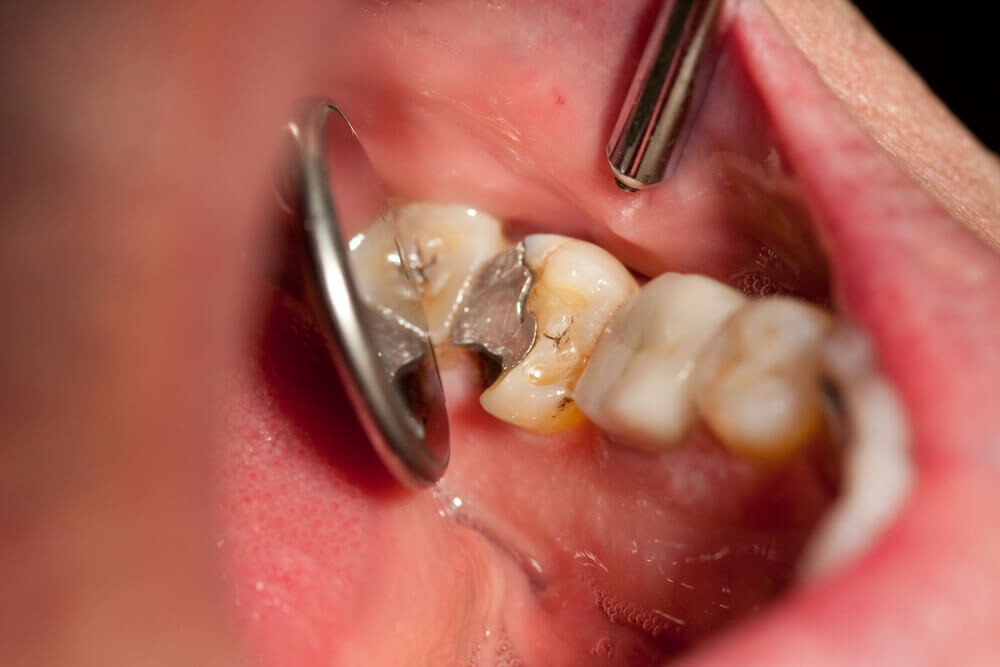

When building a foundation for a healthy body, people traditionally focus on exercise, nutritious foods and the occasional doctor visit. Although mouth health tends to get overlooked in the process, it can make a profound difference on how you feel in other aspects of life. More commonly known as teeth grinding, bruxism is one mouth malady that shouldn't go untreated.

Is it common for you to wake up in the morning with a sore jaw or a headache? Do you at times clench your teeth? Until you have a dental examination or experience pain, you may not know that you are a victim of a condition known as bruxism. Bruxism is the clenching, gritting or grinding of teeth. Many individuals do not know that they clench their teeth as they mainly do it when asleep. Bruxism usually takes place during the early hours of the night and can result to irregular sleep patterns. In some people grinding and clenching can be fairly audible, while other people tend not to make any sound hence they do not know that they suffer from teeth grinding until they are told by a dentist. Apart from causing discomfort, bruxism can destroy dental restorations.

Signs and Symptoms

Bruxism has many symptoms that are similar to those of other conditions. Consult your dentist if you're concerned about:

Diminished tooth enamel and increased tooth sensitivity.

Jaw soreness or tight jaw muscles.

Grinding of the teeth loud enough to wake up your partner.

Flat, loose or chipped teeth.

A headache that begins at your temples.

Prevention and Treatment

If you suspect you suffer from bruxism, start listing any symptoms and call attention to them at your next dental appointment. Your dental professional may want to perform a full examination to confirm any symptoms or signs for sure, and then determine the reasons they have occurred. In the interim, he or she may prescribe a mouth guard to relieve any damage already done from grinding, or perform a dental procedure to correct any problems related to tooth alignment. Discussing stress reduction methods is another option if you haven't undertaken them.